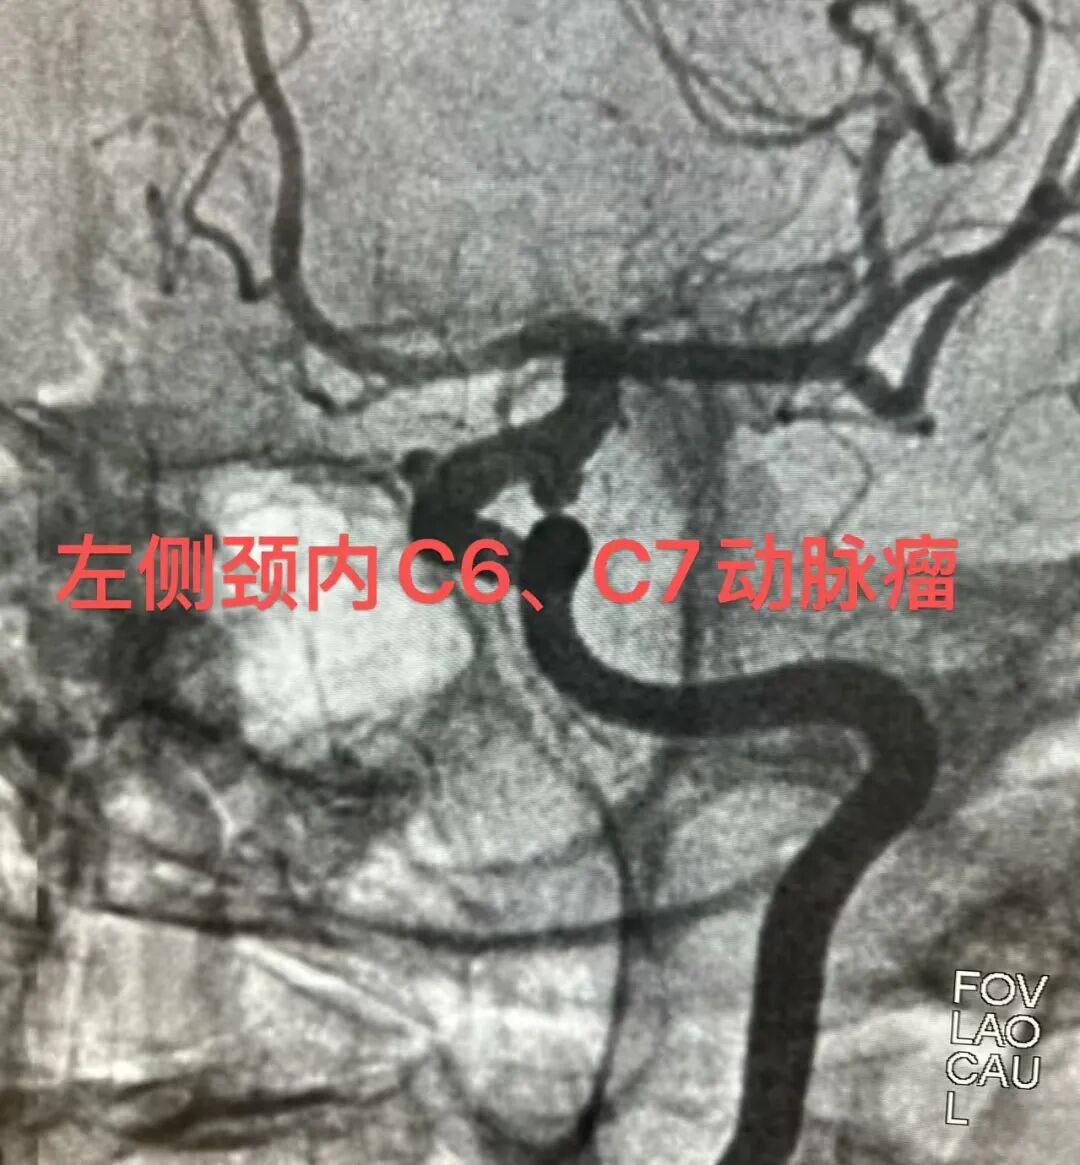

这位患者被确诊为脑动脉瘤,这颗颅内的“不定时炸弹”随时可能破裂,致死致残率极高。DSA明确显示:左侧颈内动脉眼段及后交通段各存在一枚动脉瘤。鉴于双动脉瘤位置邻近且位于同侧血管,为一次性处理并重建载瘤动脉,同时降低多枚支架植入或常规弹簧圈栓塞的复杂性与远期复发风险,经术前充分评估,选择行血流导向装置(密网支架)植入术。

手术室内,DSA机臂缓缓转动,屏幕上的血管影像清晰如画。导管精准到位,密网支架徐徐打开,如一张精密的“防护网”覆盖在瘤颈之上。无需填塞,仅靠改变血流动力学,便让动脉瘤内的血液“安静”下来,逐渐走向血栓闭合。

术后造影显示:支架打开贴壁良好,动脉瘤内造影剂明显滞留,载瘤动脉血流通畅。意味着神经内科介入团队成功将这颗“炸弹”拆除了。